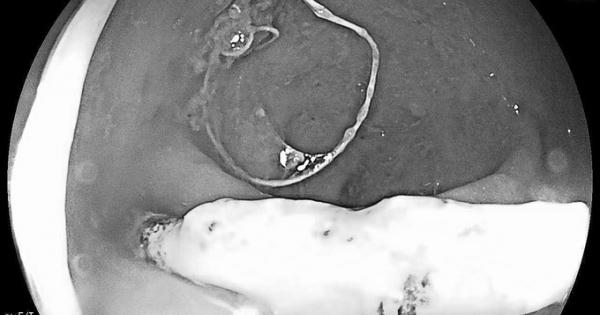

Bệnh nhân nữ, 26 tuổi ở Quảng Bình đi khám phát hiện vòng tránh thai đâm xuyên thành trực tràng nếu không phát hiện kịp thời có nguy cơ thủng ruột